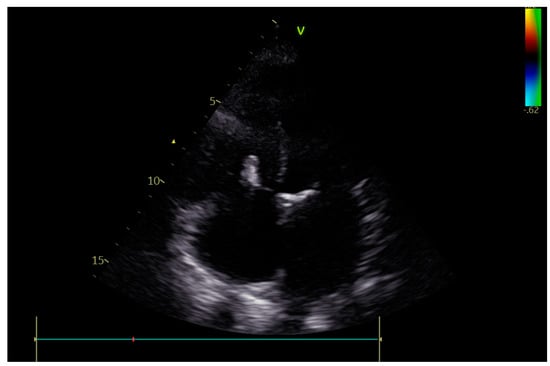

Cardiac Post-Chest Radiotherapy Complications in a 50-Year-Old Patient with Hodgkin Lymphoma

2. Case Report